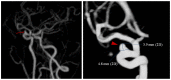

Background and purpose: Contrast enhanced MRA (CE-MRA) can help to overcome the limitations of other techniques to clearly display the details of cerebral aneurysms at 1.5-T MR system. We investigated the prevalence of unruptured cerebral aneurysms (UCAs) using three dimensional (3D) CE-MRA in a tertiary comprehensive hospital in China.

Materials and methods: The cases were prospectively recorded at our hospital between February 2009 and October 2010. 3D CE-MRA, interpreted by 2 observers blinded to the participants' information, was used to identify the location and size of UCAs and to estimate the overall, age-specific, and sex-specific prevalence.

Results: Of the 3993 patients (men: women = 2159:1834), 408 UCAs were found in 350 patients (men: women = 151:199). The prevalence was 8.8% overall (95% CI, 8.0-10.0%), with 7.0% for men (CI, 6.0-8.0%) and 10.9% for women (CI, 9.0-12.0%). The overall prevalence of UCAs was higher in women than in men (P<0.001) and increased with age both in men and women. Prevalence peaked at age group 75-80 years. Forty-two patients (11.7%) had multiple aneurysms, including 10 (2.9%) male patients and 32 (9.1%) female patients. The most common site of aneurysm was the carotid siphon, and most lesions (71.3%) had a maximum diameter of 3-5 mm.

Conclusion: This hospital-based prevalence study suggested a high prevalence (8.8%) of UCAs and most lesions (71.3%) had a maximum diameter of 3-5 mm observed by 3D CE-MRA. Because the rupture of small cerebral aneurysms was not uncommon, an appropriate follow-up care strategy must be formulated.